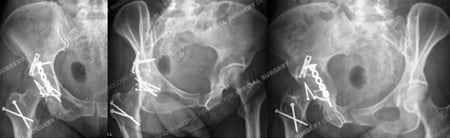

Radiographs at 5 months postoperative revealing healed femoral head and acetabular fractures.

A 64-year-old female was involved as a passenger in a high-speed motor vehicle accident while on vacation in Nicaragua. She was taken to a local hospital and diagnosed with a right-sided posterior hip dislocation that was closed reduced. She also had an associated right-sided Pipkin IV Type fracture of the femoral head with associated Posterior Wall Type fracture of the acetabulum. After placement of skeletal traction she was transferred to the care of Dr. David L. Helfet at the HSS Orthopedic Trauma Service through a medical flight facilitated through her travel insurance. Open reduction and internal fixation (ORIF) was performed through a Kocher-Langenbeck surgical approach with an anterior surgical hip dislocation. The Posterior Wall fracture was reduced and fixed with one-third tubular and pelvic reconstruction plates and screws. The femoral head fracture was reduced and fixed with sub-articular screws and preservation of the blood supply, reduction, hip stability, and adequate hardware placement was confirmed. At the time of her latest follow-up at 5 months radiographs reveal healed acetabular and femoral head fractures and maintenance of reduction with mild degenerative changes in the hip joint.